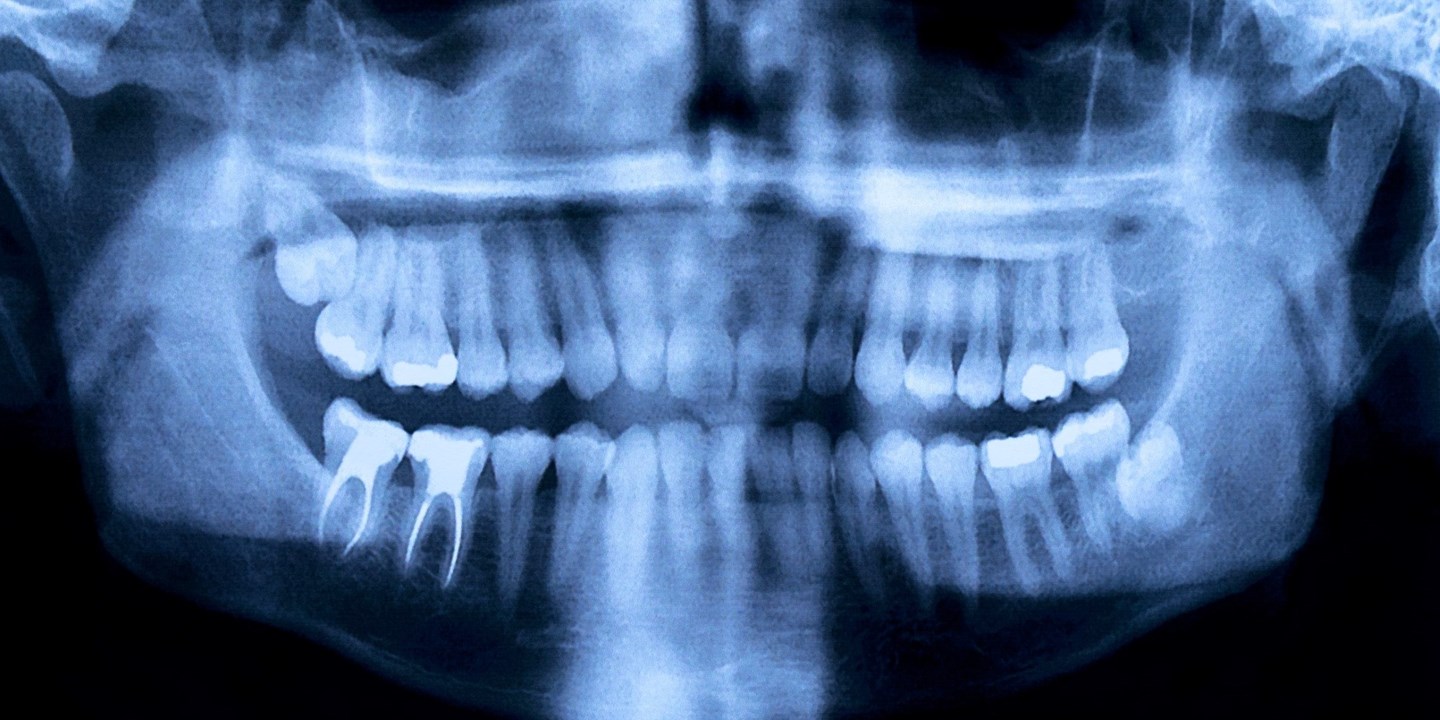

Panoramaröntgen

Inför vissa typer av behandlingar kan det vara nödvändigt med en panoramaröntgen. Vi skickar remiss vid behov av en panoramaröntgen.